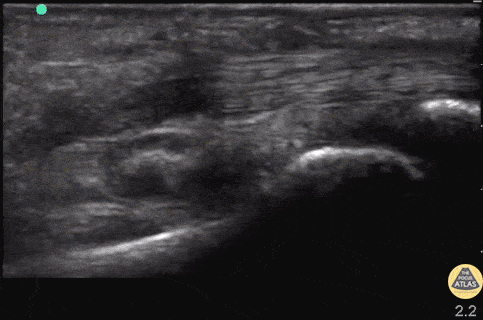

Musculoskeletal - Flexor Tendons of Hand (normal)

Patient with atraumatic pain and swelling of R proximal phalanx. Flexor tenosynovitis was considered but view revealed normal flexor tendons without surrounding hypoechoic fluid or inflammation of the tendon. Keep in mind this is not a sufficient rule out test. In this image, the tendon can be seen flexing and extending with the proximal and distal phalanges articulating on each other. Drs. Hannah Moreira and John F Kilpatrick - Kings County/SUNY Downstate Emergency Medicine